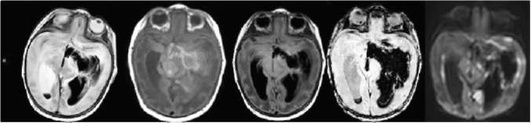

Интенсивность МР-сигнала от гематомы на ДВИ и ИКД-картах меняется в зависимости от стадии развития гематомы и менее специфична, чем при ИИ. МРТ-режимами для диагностики ГИ являются Т2*-градиентное эхо или SWI/SWAN режимы, позволяющие с высокой чувствительностью и специфичностью визуализировать наличие крови во все сроки проведения исследования и должны обязательно быть включены в МРТ-протокол обследования больных с ОНМК. Стандартные (Т2/Т1 ВИ) режимы исследования обладают наибольшими чувствительностью и специфичностью в более поздние сроки заболевания (подострый период), примеры интрапаренхиматозных гематом на разных сроках организации показаны на рис. 5-10 - 5-14 и табл. 5-6.

image

Рис. 5-10. Острые нарушения мозгового кровообращения у ребенка 5 лет. Магнитно-резонансная томография в острой стадии ишемического инсульта. (24 ч от момента развития ишемического инсульта). МРТ-изображения головного мозга в режиме диффузионно-взвешенных изображений (b1000) (а), с соответствующим ИКД (б), Т2 ВИ (в) и FLAIR (г) в аксиальной проекции. В правом полушарии большого мозга области подкорковых структур определяется ишемический очаг повышенного сигнала в режимах Т2, FLAIR и в диффузионно-взвешенных изображениях с пониженным ИКД, слабо пониженного в Т1 (д)

Острейшая стадия геморрагического инсульта (до 24 ч от начала заболевания) по данным МРТ характеризуется изоинтенсивным в Т1-ВИ сигналом, слабым повышением интенсивности МР-сигнала с участками пониженного в режимах Т2-ВИ, FLAIR и ДВИ, пониженного - в SWI. Имеются признаки объемного воздействия на прилежащие структуры головного мозга. Острая стадия ГИ по данным МРТ (2-3 сут от начала заболевания) характеризуется гипоинтенсивным МР-сигналом в режимах SWI, Т2-ВИ, FLAIR и ДВИ (см. рис. 5-13), что обусловлено преобладанием парамагнетика - дезоксигемоглобина, который благодаря эффекту магнитной чувствительности имеет «темный цвет» в большинстве используемых режимах в этот период организации ГИ. Особенно это проявляется в импульсной последовательности, чувствительной к компонентам крови (SWI или градиентное эхо Т2* GE (gradient Echo)). Зона перифокальных изменений, окружающая ГИ, имеет гиперинтенсивный МР-сигнал в режимах Т2-ВИ и FLAIR (см. рис. 5-14).